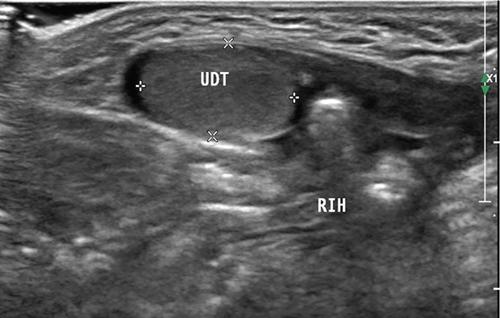

Fig. 11.8.3Inguinal US scan of a 2-month-old male child shows undescended right testis (UDT in cursors) at superficial inguinal ring with associated inguinal hernia (RIH). Clinically the child presented with empty right hemiscrotum since birth.

Visibility of nonpalpable intraabdominally located testis is impaired by bowel gases at US, however, with experienced hands the same can be depicted on ultrasound deep to internal inguinal ring, adjacent to iliac vessels and lateral bladder wall. Tracking the cord technique is also a valuable sign in localizing nonpalpable testis (also ectopic testis) (Fig. 11.8.3).